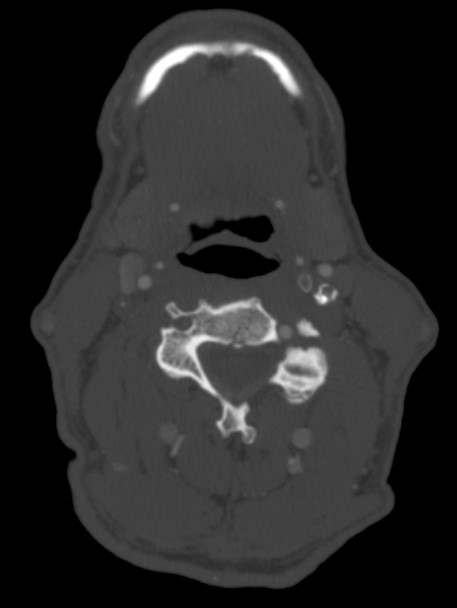

Much research is being done in order to identify carotid artery imaging findings that can help predict stroke. Various plaque characteristics have been examined including echolucency, fat content and calcium content. To date, there is no good prediction model.